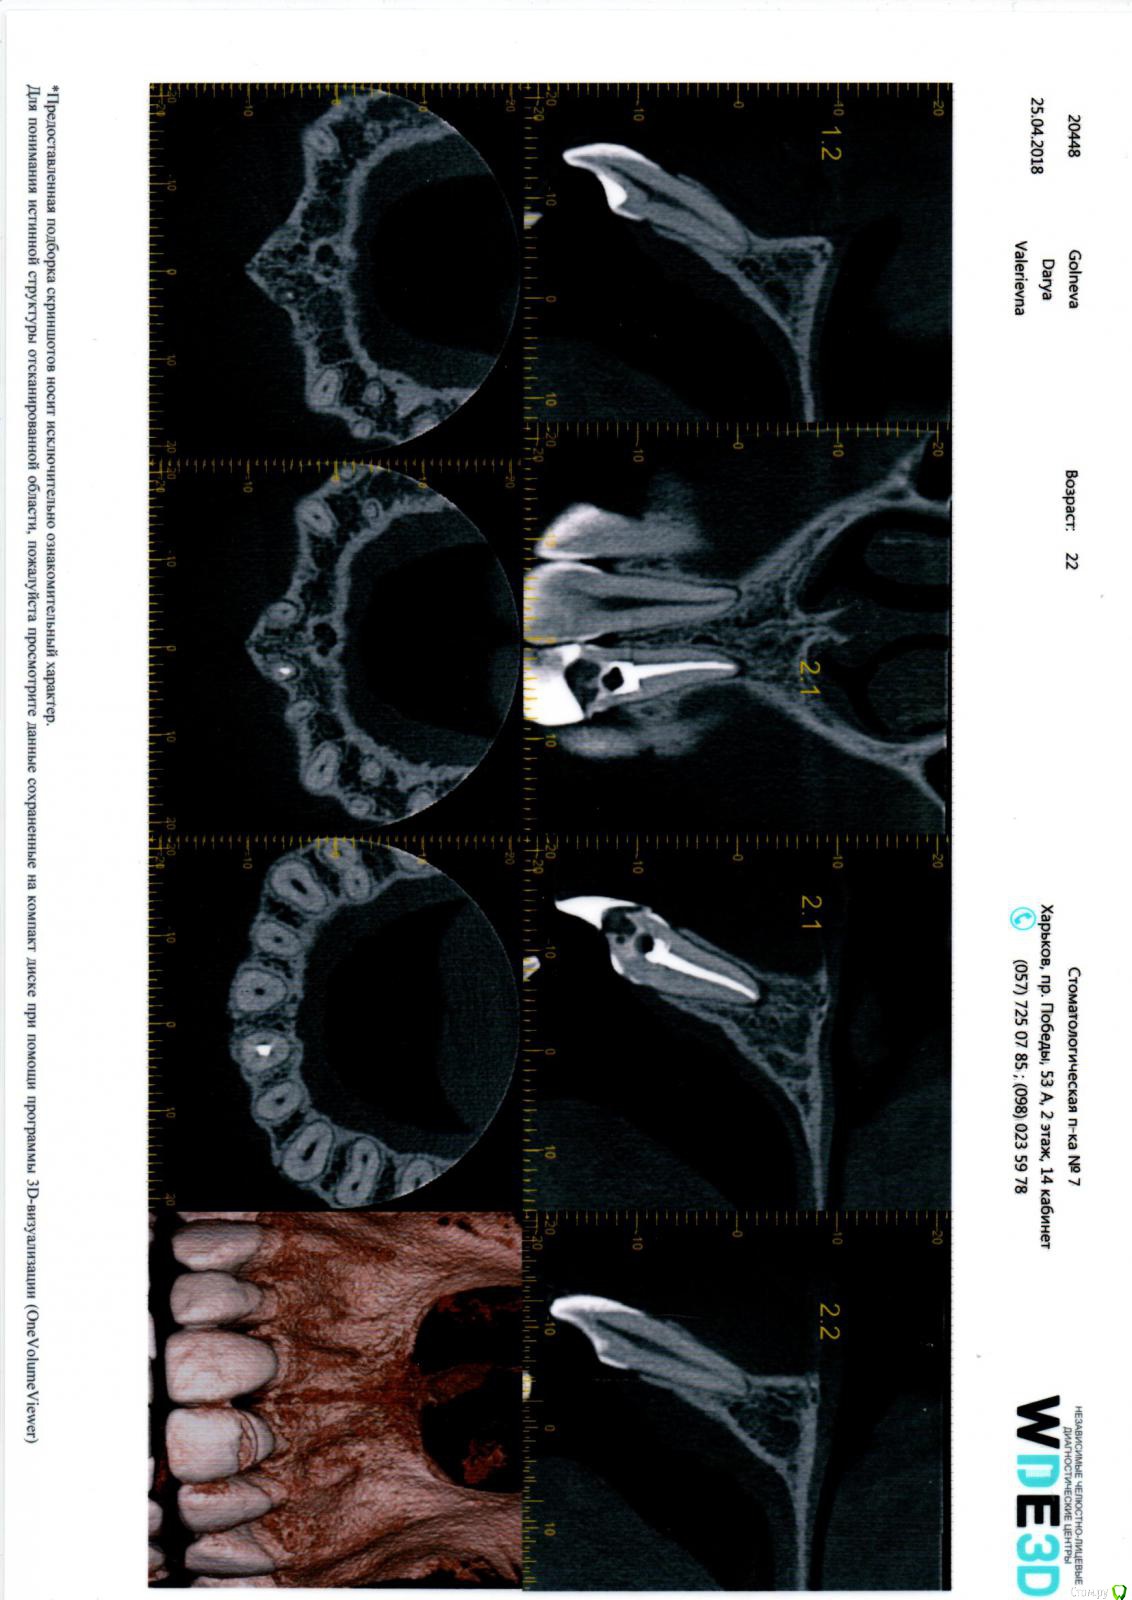

golneva Опубликовано 24 апреля, 2018 Поделиться Опубликовано 24 апреля, 2018 (изменено) Добрый день. Около трех месяцев назад не вписалась в дверной проем с утра и сломала передний верхний зуб. Пол зуба просто откололась. Сразу же обратилась к врачу (врач из очень опытных, наверное больше 30 лет стажа, посоветовали блин). Удалил нерв, залепил "лекарство" через три дня запломбировал канал. Из вариантов лечения предложил только одеть металлокерамику и все. Согласилась потому что никогда не сталкивалась с протезированием, думала что лет до 35 все будет ок, мне 22 года, только 2 пломбы в зубах. После установку вкладки ( хотя это трудно назвать вкладкой) зуб начал болеть, болел очень сильно, врач выписал антибиотики, очень сильный препарат с кучей побочных эффектов, которые я ощутила неподетски, зуб стал болеть чуть меньше и он решил что можно обточить, наколол анестезию такую что в глазах двоилось, но во время обточки он не использовал ни воду, ни десну не защитил и больно было так как будто он меня по живому режет. Прописал другой антибиотик и хлористый кальций, через неделю закончил с обтачиванием, зуб практически не болел. После обтачивания боль слегка усилилась, но когда нужно было одеть коронку он уже почти не болел. Коронка не подошла идеально и врач снова решил обтачивать зуб, и снова было дико больно даже с сильной анестезией. Я говорила что мне больно, врач говорил что я ему вру. Когда я уже не могла терпеть он просто вручил мне в руку коронку и выпроводил. Вся эта канитель длилась чуть больше месяца. В тот же день я пошла к другому врачу, мне сразу сделали снимок где видно что у мня не допломбирован канал, вкладка это просто кусок железки, и между вкладкой и пломбой в канале пустота. На следующий день сделала КТ по совету доктора, он думал что треснул корень. Корень был целым. Доктор достал вкладку (доставал 3 часа), неделю я ходила с "лекарством" с йодом, потом дней 10 с кальцием, канал запломбировали недели три назад. Перед пломбирование зуб не болел совсем. Хожу с временной коронкой, он не болел ни при накусывании, ни при постукивании. Запломбировали хорошо и корень целый. После пломбировки зуб был чувствительным, через неделю был назначен прием чтобы сделать слепок для вкладки, но зуб побаливал и ничего не делали. Доктор сказал подождать надо. Сейчас после пломбирования (прошло уже 3 недели) зуб побаливает при накусывании, при постукивании, даже если прижать его губой он побаливает. Но боль странная, не ноющая как была раньше, а похоже на укол. Ка будто сильнейшая чувствительность, эту ощущение в последние сутки все время, как будто ем лед. если оценить по десяти бальной шкале то это где-то от единицы до трех.может кто-то сталкивался с таким, я не знаю что делать. Есть снимки только сразу после удаления нерва и через месяц после этого. Срезы КТ прилагаю, но только сбоку. Остальные снимки в клинике. Что это просто чувствительность, авитаминоз, фантомные боли??SLX+002.BMP Изменено 24 апреля, 2018 пользователем golneva Ссылка на комментарий

golneva Опубликовано 25 апреля, 2018 Автор Поделиться Опубликовано 25 апреля, 2018 Срез на томограмме после окончательной пломбировки?нет, это после первой пломбировки неудачной. Снимки после окончательной находятся у врачей. Там канал запломбирован хорошо. И материал не вышел за пределы. Возможно ли что у меня побаливает просто десна от временной коронки? От зуба осталось очень мало, первый врач сточил его безбожно, да и когда доставали вкладку, то тоже мальца зуба ушло, и временной коронке практически не за что зацепиться и она слегка пошатывается. Возможно ли что болезненные ощущение из-за этого? Или это реакция такая на пломбировочный материал? Или у меня сам канал не герметичный? что посоветуете? сделать еще одно КТ? И стоит ли задуматься о имплантации? это все таки передний зуб. Ссылка на комментарий

golneva Опубликовано 25 апреля, 2018 Автор Поделиться Опубликовано 25 апреля, 2018 меня смущает темнота на верхушке корня левой единички. Или так и должно быть? Спасибо всем участникам за ответы. Ссылка на комментарий

golneva Опубликовано 25 апреля, 2018 Автор Поделиться Опубликовано 25 апреля, 2018 (изменено) прилагаю еще две ссылки на скиншот это кт 1,5 месяца назад с вкладкой и проблемным каналом https://pp.userapi.com/c846019/v846019009/31dd8/jYA-TT3sZI4.jpgэто сегодня без вкладки с перелеченым каналом fhttps://pp.userapi.com/c846019/v846019009/31de2/cRZp8W0TM2E.jpg Изменено 25 апреля, 2018 пользователем golneva Ссылка на комментарий